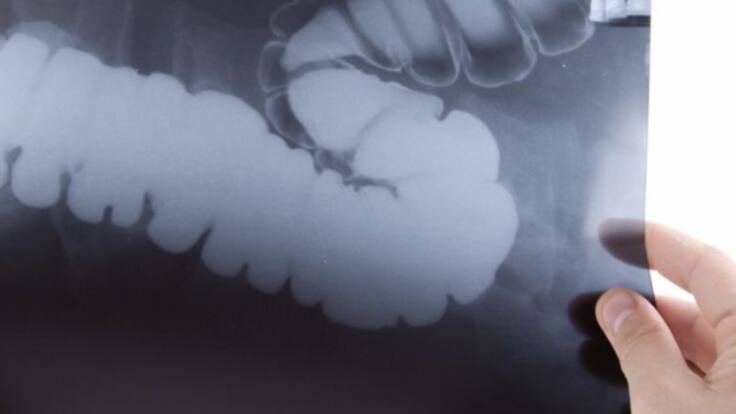

Preocupación por el incremento de casos de cáncer colorrectal en menores de 50 años

Preocupante aumento del cáncer colorrectal en menores de 50 años

La Dra. Fernández Montes es oncóloga en el Complejo Hospitalario Universitario de Ourense (CHUO) y miembro de la junta directiva del Grupo de Tratamiento de los Tumores Digestivos (TTD), se muestra muy preocupada por el notable incremento de la tasa de incidencia de cáncer colorrectal en personas de entre 20 y 49 años que se está produciendo en el último cuarto de siglo. El abandono de la dieta mediterránea, el tabaquismo, el consumo de alcohol y la vida sedentaria parecen ser las responsables de esta situación, agravada por un diagnóstico tardío al no ser habitual hasta hace poco tiempo este tipo de cáncer en este grupo de población. Uno de cada cuatro nuevos casos de esta modalidad de cáncer en jóvenes se diagnostica en estadios avanzados y, por lo tanto, con peor pronóstico de curación.

El Grupo de Tratamiento de los Tumores Digestivos ha lanzado la campaña "Sospechosos Habituales", con la intención de hacer consciente al conjunto de la sociedad la situación del cáncer de colón. La idea es hacer llegar a la población recomendaciones para evitar los factores de riesgo sobre los que podemos y debemos actuar, estos son algunos de ellos:

Consumo de carnes procesadas, tabaco, alcohol, obesidad, sedentarismo...caminar media hora al día una vez diagnosticado de cáncer colorrectal reduce el riesgo de mortalidad en un 38%. Incrementar la ingesta de verduras y vegetales, tomar más fibra ayuda en la prevención. Otra recomendación es participar en los cribados para la detección precoz de la enfermedad, ahora se realiza entre la población de más de 50 años, pero la Dra. Fernández Montes está convencida que habrá que ampliar la la franja de edad comenzando a los 45.